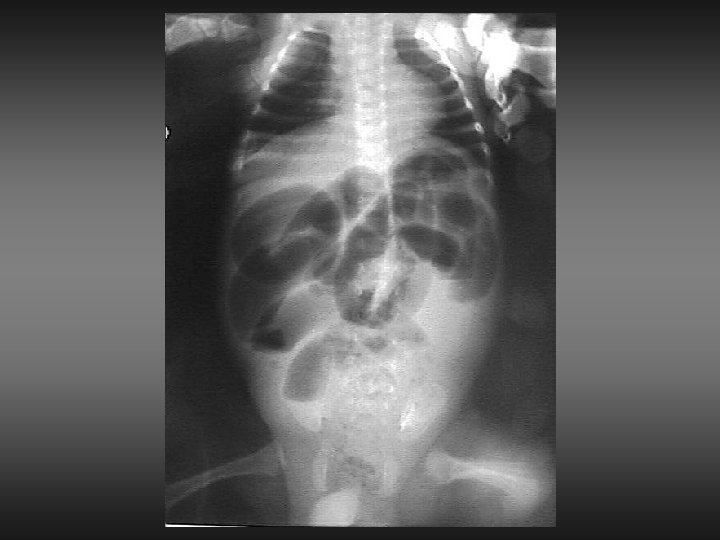

ATASCAMIENTO DAÑO INTESTINAL DAÑO TESTICULAR